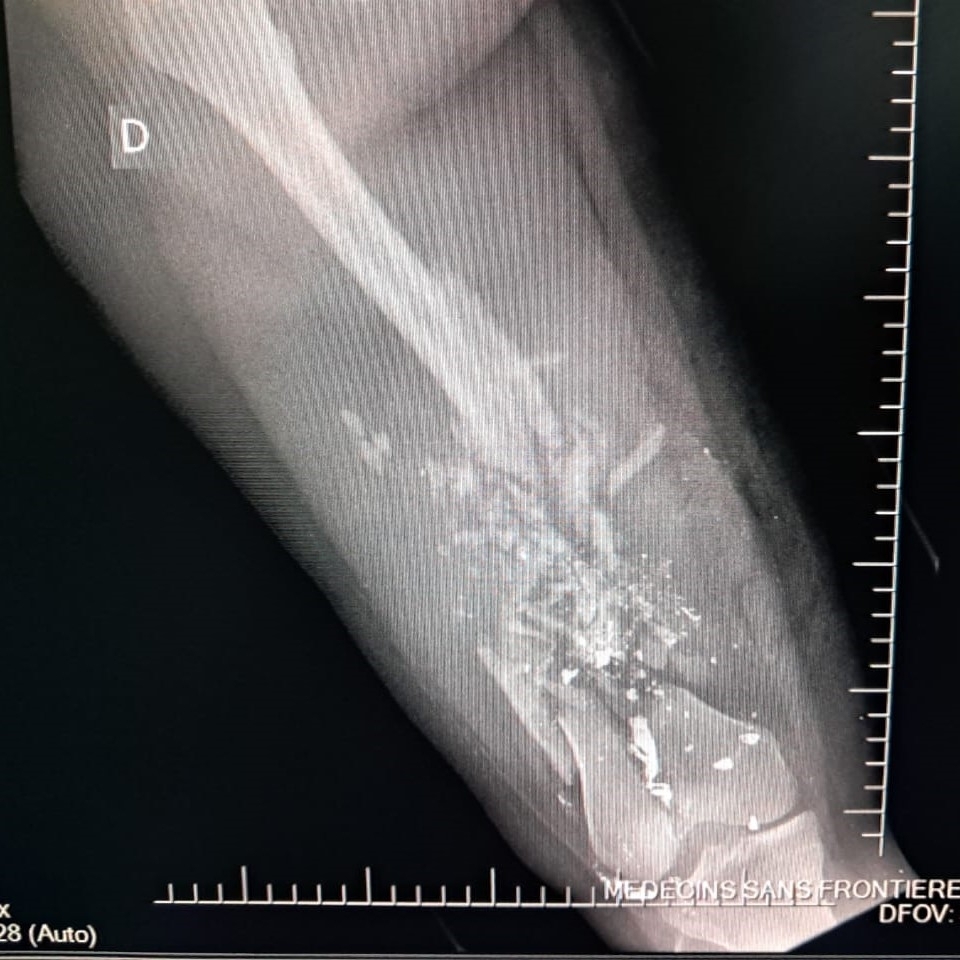

Between January and June 2025, MSF teams assisted 2,600 survivors of sexual violence, admitted 13,300 patients to emergency rooms and treated 2,267 survivors of violence. Among these, 26 per cent were minors, compared to 11 per cent in 2024. Most minors were under the age of 15 and one third were girls. Thirty per cent of all minors admitted for violence-related injuries suffered gunshot wounds.

On Sept. 20, 17 wounded people were treated at the MSF hospital in Drouillard following a drone attack carried out the same day in the Cité Soleil neighbourhood. Among them were two men who were dead on arrival, another man who died while being transferred, 10 women — one of whom died on the way to MSF’s trauma hospital in Tabarre — and three children who tragically did not survive their injuries. Two more women injured in this attack died at the nearby Isaïe Jeanty maternity hospital, where MSF is also working.

This violence is occurring in the context of a territorial conflict with the people directly on the frontlines, trapped between the threat of explosive drones and the brutal violence of armed groups. These groups loot and burn homes, destroy neighbourhoods, terrorize communities and increasingly use sexual violence as a weapon of control, punishment and extortion.